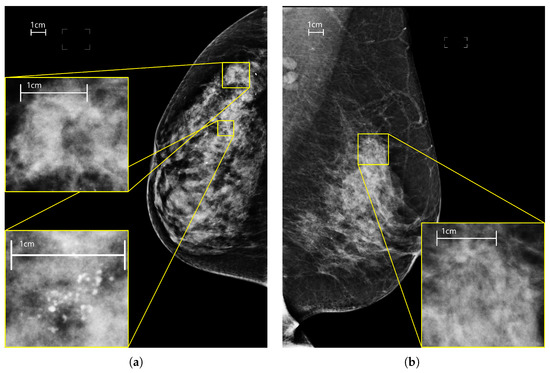

Lesions have different characteristics in shape, appearance, size and sparseness: masses are space-occupying lesions with a typical diameter of a few centimeters; calcifications are tiny deposits of calcium with a dimension typically less than a millimeter almost always grouped in a cluster; asymmetries are defined as unilateral deposits of fibroglandular tissue; architectural distortions refer to disruptions of the normal pattern of tissue with no definite mass visible. In Figure 1 mammograms with different types of lesions are shown. In this context, we want to analyze the performance of CNNs and transformers, which are based on two different paradigms (locality and global attention), with respect to lesions with different spatial patterns (dense and sparse). Other characteristics of the lesions, especially the size, make the input images resolution a crucial factor for the detectability of malignant findings and the correct classification of mammograms. Therefore we conducted a series of experiments by varying the input resolution from to with a 128-pixel step on the image width using two networks, an EfficientNet-B0 and a SwinV2-B. For each experiment, we also computed per-lesion metrics to highlight the correlation between input resolution, performance by type of lesion, and network architecture. Our major contributions are:

Figure 1.

Mammograms of different views, laterality and containing different lesions. (a) right cranio-caudal with two lesions: a calcification cluster and a mass. (b) left medio-lateral oblique with a focal asimmetry. (c) right medio-lateral oblique with an architectural distorsion. (d) left cranio-caudal containing a mass with calcifications inside.